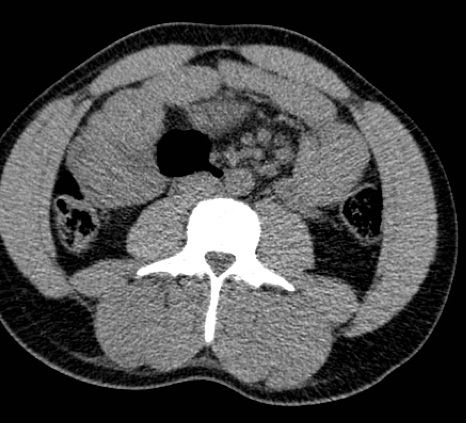

Acute bilateral paraspinal compartment syndrome

Patient is a bit of a gym junkie and did a particularly strenuous session prior to the onset of symptoms. Patient had hematuria with 2 days of severe low back pain radiating into the groin and right leg. Khan et al. Acute paraspinal compartment syndrome. A case report. J Bone Joint Surg Am. 2005 May; 87(5):1126-8.

Courtesy Bill Breidahl, MD